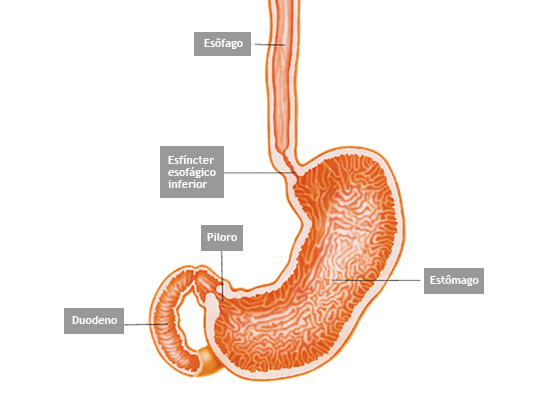

O que é o piloro ?

Piloro é o esfíncter que fica na poção final do estômago, na sua transição com o duodeno. Com os movimentos de contração do estômago o piloro se abre a permite que o conteúdo estomacal passe para o duodeno.

Estenose de piloro

Estenose do piloro é o estreitamento parcial ou total do mesmo que impede a progressão do conteúdo do estômago para o duodeno.

Estenose do piloro pode acontecer por 3 causas principais: